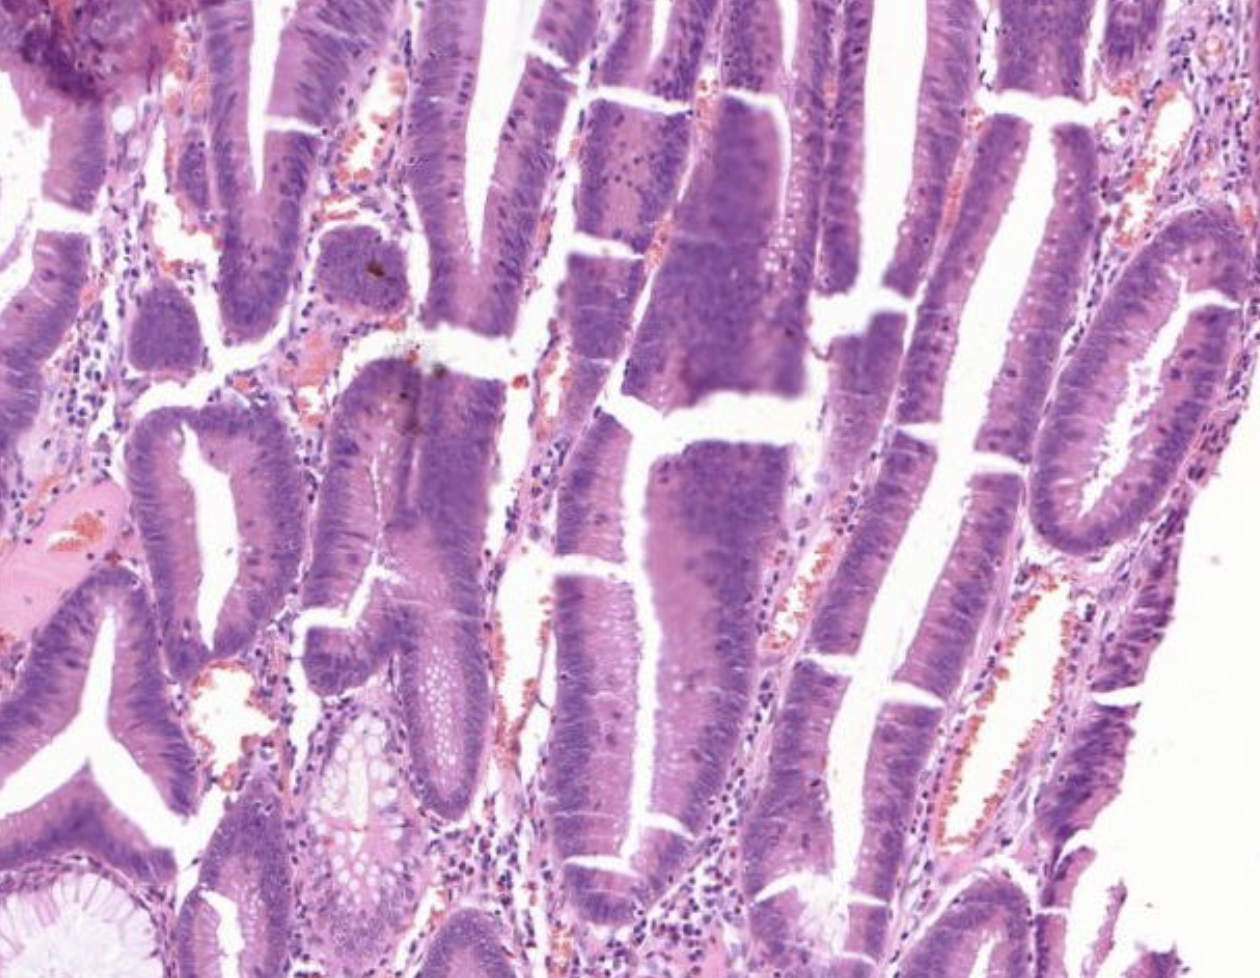

40) Was ist hier für eine Schleimhaut zu sehen?

Histopathologisches Bild: Kolonschleimhaut

Hier zu sehen ist eine Colon Mukosa (Schleimhaut).

Zu erkennen daran, dass es nur Krypten und keine Zotten gibt.

40) WElches Gewebe ist hier zu sehen?

Es zeigt sich die Mukosa des Colons. Daran zu erkennen das keine Zotten aber Krypten zu sehen sind. Kennzeichen einer guten Krypte: Bis oben hin becherzellartig.

Was zeigt sich im bezug auf die Mrophologie bei sicht auf diese Krypten?

Es zeigt sich das coronal an de Krypten die Becherzellen fehlen am Grund jedoch noch einige Becherzellen in den Untenständigenzellen vorhanden sind

Diese Zellen Proliferieen aberant, das bedeutet es sollten sich eigentlich überall in der Krypte zellen mit Becherzellen darin befinden, die neu gebildeten Zellen, da proliferiert stehts von unten wird, besitzen jedoch keine Becherzellen

40) Wie nennt man diese Tumorerkrankung?

Tubuläres Adenom der colon schleimhaut. Kerne vergrößert, keine Becherzellen darin vorhanden. Zellbild sieht anders aus.